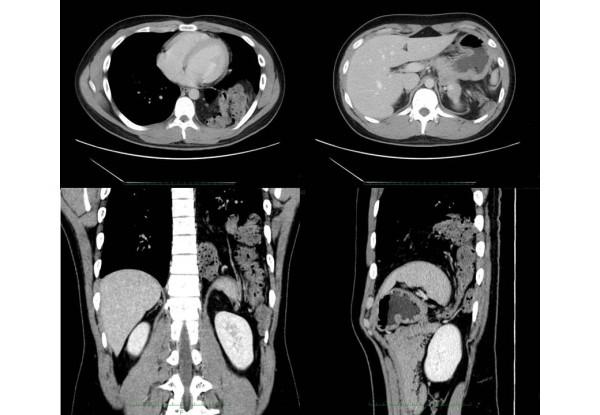

We present a 17-year-old Japanese boy with left-upper-quadrant pain for two months. Chest radiography showed an elevated left hemidiaphragm. Computed tomography revealed a congenital diaphragmatic hernia. The spleen and left colon had been displaced into the left thoracic cavity through a left posterior diaphragmatic defect. We diagnosed a Bochdalek hernia. Surgical treatment was performed via a thoracoscopic approach. The boy was placed in the reverse Trendelenburg position and intrathoracic pressure was increased by CO2 gas insufflations. This is a very useful procedure for reducing herniated contents and we were able to place the herniated organs safely back in the peritoneal cavity. The diaphragmatic defect was too large to close with thoracoscopic surgery alone. Small incision thoracotomy was required and primary closure was performed. His postoperative course was uneventful and there has been no recurrence of the diaphragmatic hernia to date.

我们报告一名17岁的日本男孩,左上腹疼痛两个月。胸部X线片显示左半膈肌抬高。计算机断层扫描显示先天性膈疝。脾脏和左结肠通过左后膈肌缺损移入左胸腔。我们诊断为波氏孔疝。通过胸腔镜手术进行治疗。男孩置于头低脚高位,通过二氧化碳气体注入增加胸腔内压力。这是一种非常有用的减少疝内容物的方法,我们能够将疝出的器官安全地放回腹腔。膈肌缺损太大,仅通过胸腔镜手术无法闭合。需要小切口开胸并进行一期缝合。他术后恢复顺利,迄今为止膈疝未复发。